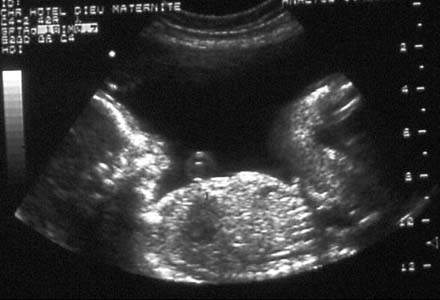

Micrognathisme avec rétrognathisme